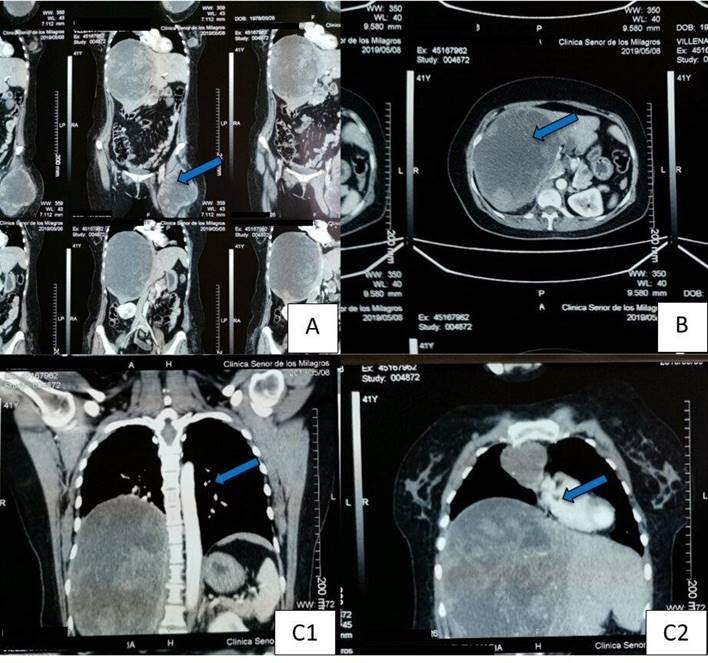

La tomografía computarizada (TC) reveló un gran proceso expansivo en el hígado y en el muslo izquierdo, así como múltiples lesiones nodulares mediastínicas y pulmonares (Figura 2). Una biopsia del muslo izquierdo y de la mama izquierda confirmó una neoplasia de células fusiformes con atipia relacionada con un leiomiosarcoma de grado 2.

Figura 2 TC. (A) TC de abdomen y muslo que muestra un extenso proceso expansivo en el hígado y muslo derecho proximal con densidad heterogénea relacionada con la metástasis. (B) TC de abdomen que muestra una lesión expansiva heterogénea en hígado. (C1 y C2) TC de tórax que muestra un proceso expansivo en el hígado. (C1) Pequeños nódulos pulmonares (C2) Una lesión expansiva en el mediastino.